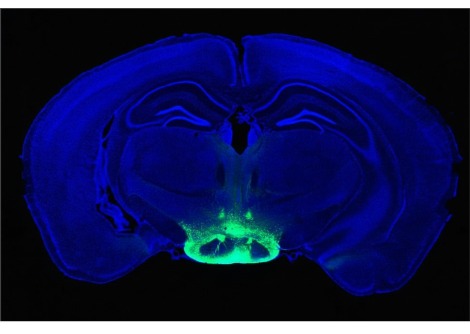

وفي عام 2025 أضافت لجنة نوبل فصلًا جديدًا إلى هذا التاريخ المجيد، إذ منحت جائزة نوبل في الطب لثلاثة علماءٍ أسهموا في كشف أسرار "التسامح المناعي المحيطي" — تلك الآلية الدقيقة التي تحفظ توازن جهاز المناعة بين الدفاع عن الجسم ومنع مهاجمة أنسجته الذاتية. كان هذا الاكتشاف ثمرة عقودٍ من البحث والتجريب، ومثّل تحوّلًا جذريًّا في فهم الطب الحديث لأصل الأمراض المناعية الذاتية. وقد جاء هذا الإنجاز تتويجًا لأعمال فريد رامزدل وشيمون ساكاجوتشي وماري برونكاو الذين كُرِّموا على إسهامهم في حل أحد أكثر ألغاز جهاز المناعة تعقيدًا، وهو كيف يستطيع هذا النظام المعقّد أن يدافع عن الجسم ضد الفيروسات والبكتيريا والخلايا السرطانية من غير أن ينقلب على نفسه ويدمّر خلاياه السليمة.